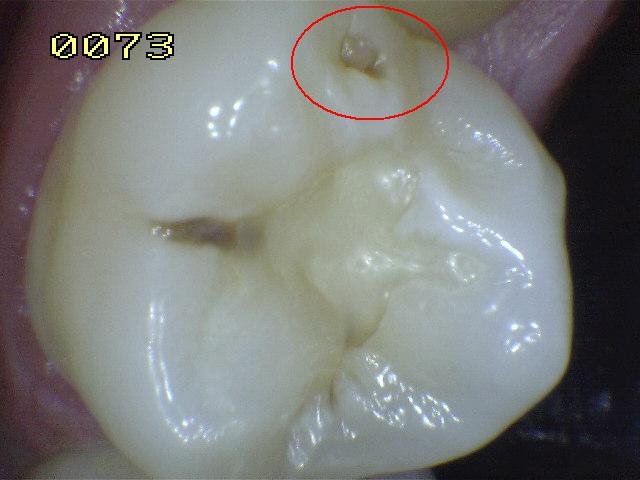

Código 1(Caries

Inicial): Primer cambio

visible en el esmalte seco

- Cuando se observa la

superficie húmeda no hay evidencia de cambio de color

que se pueda atribuir a actividad cariogénica, pero

después del secado prolongado con aire (durante

aproximadamente 5 segundos) se observa una opacidad o

pigmentación compatible con desmineralización que no es

consistente con el esmalte clínicamente sano.

- (Mancha blanca

/ marrón)